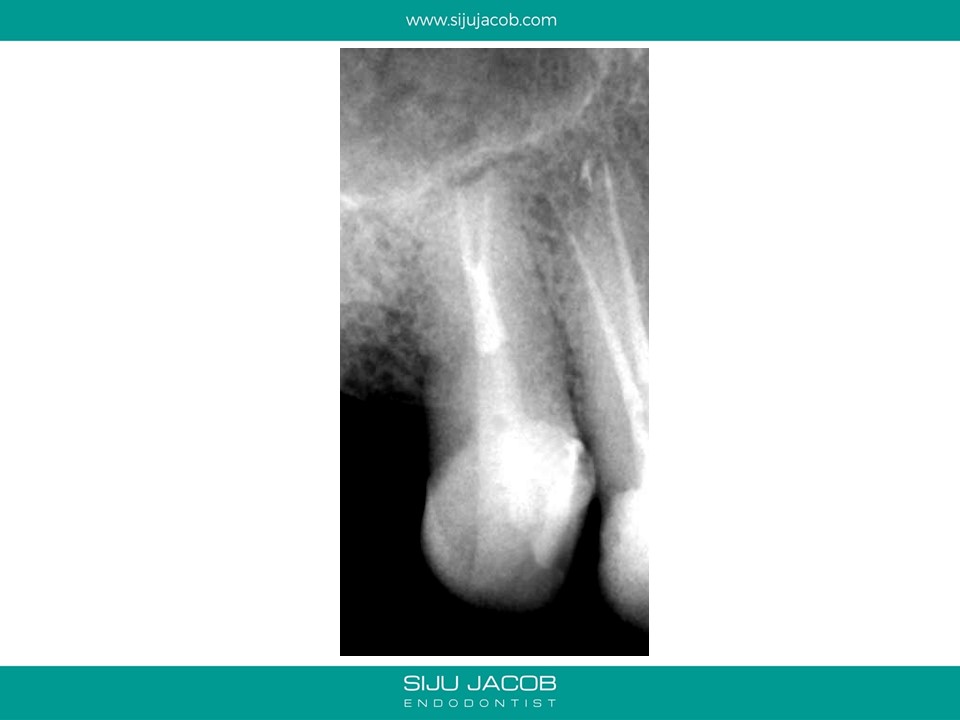

This maxillary premolar bufurcated quite deep into two canals. These type of cases are good examples of anatomy that can easily be missed without magnification.